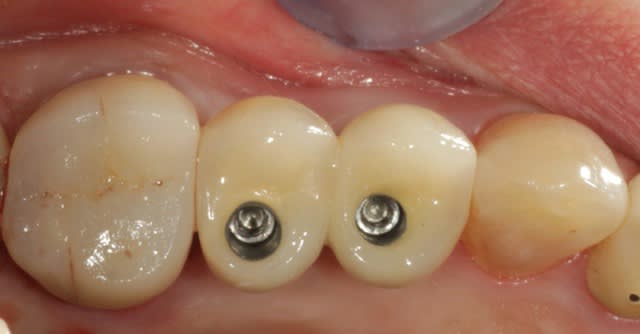

Zoli, mais j'aime pas les trous à l'occlusal...

rassure toi , ils sont bouchés.

gros avantage pour moi du transvissé sur pilier uni, les piliers ont été vissés le jour de la chirurgie et on n'y touche plus après, c'est mieux pour la gencive.